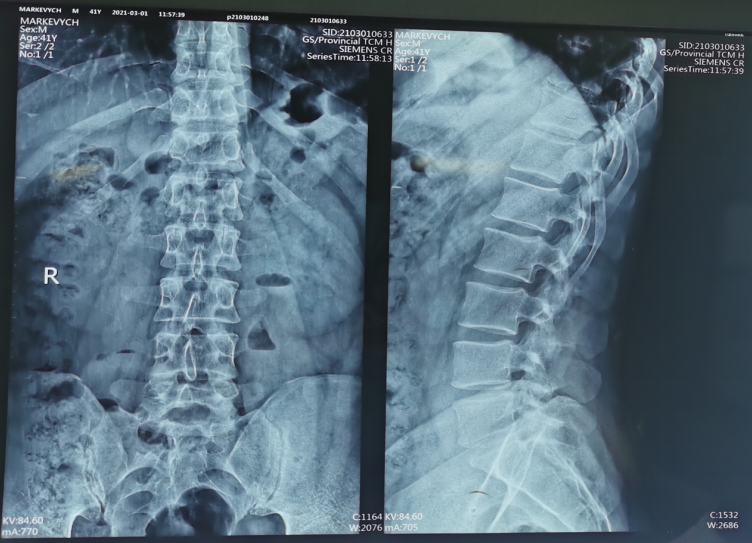

术前X线片

术前CT

术前MRI